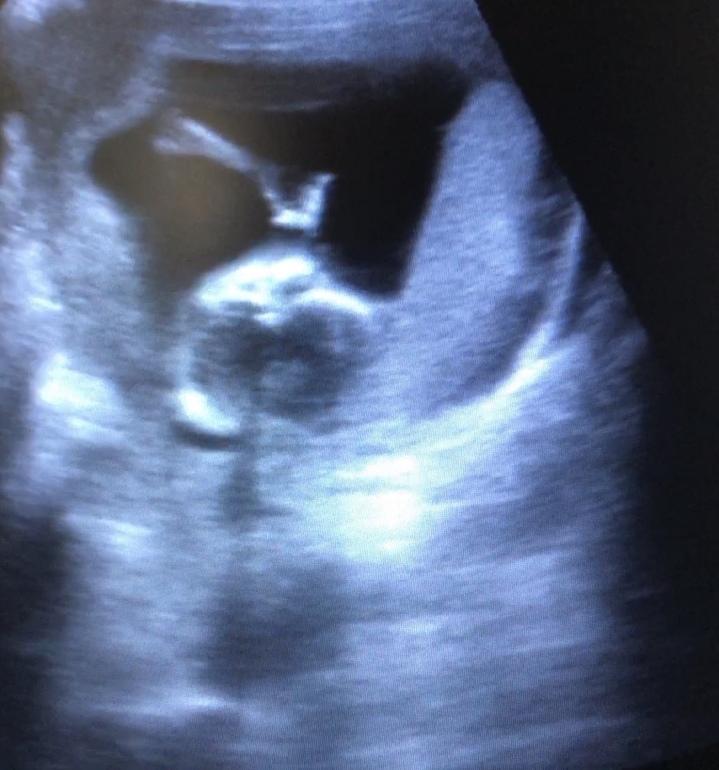

А вот так мы уже палец сосем 🥰